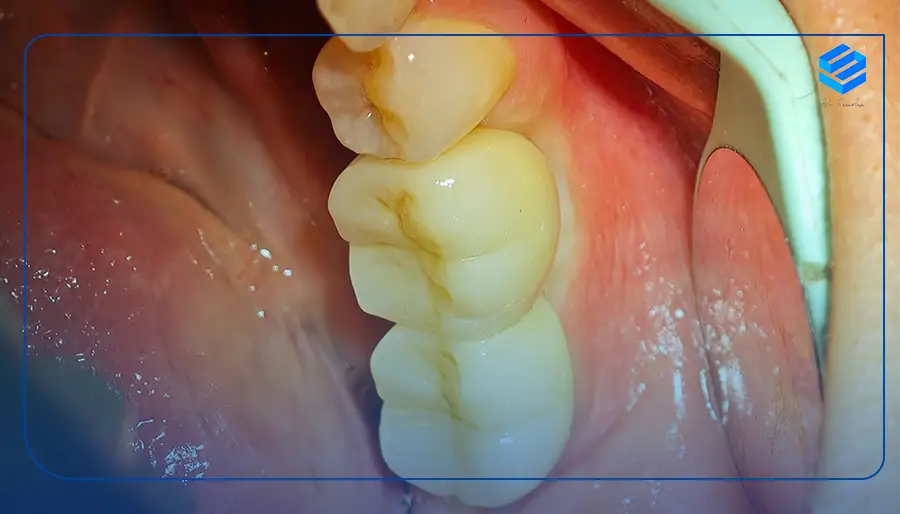

از نظر فرآیند کاشت، ایمپلنت دندان آسیاب شبیه دیگر دندانها است اما باید در نظر داشت که تمام ایمپلنتها مناسب دندان آسیاب نیستند. دندانهای آسیاب به واسطه عملکردی که دارند دارای ریشه بزرگتر نسبت به دندانهای نیش هستند. برای ایمپلنت دندان آسیاب باید از ایمپلنت اندوستئال استفاده شود.